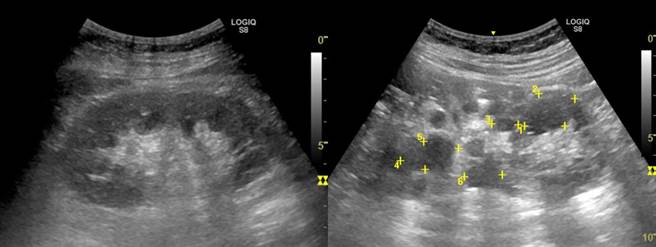

超音波比对正常健康的肾臟(左图);24岁多囊肾患者肾有水泡(黄点处)外观变形(右图)。(光田综合医院提供/王文吉台中传真)

台中24岁黄小姐的父亲患有「自体显性多囊肾」长期洗肾,多年前病逝,多囊肾因属遗传疾病,黄小姐检查也发现多囊肾第3期,年纪轻轻面临洗肾。光田综合医院肾臟科给予服用新口服药物,延缓洗肾时间,并结合国卫院引进基因检测,有助慢性肾病患者及早诊断治疗。

多囊肾是一种遗传性疾病,只要父母亲其中一人得病,儿女罹病机率是50%。光田综合医院肾臟内科主任王家良表示,多囊肾患者出生时肾臟可能就有囊肿,但初期没有明显症状,普遍在30到40岁后,因肾功能逐渐退化,才会引起高血压、背痛、腰痛、尿路结石、泌尿道感染等症状,而检查确定罹病已为时已晚。

光田综合医院副院长暨肾臟内科医师张家筑呼吁,多囊肾初期并没有特别的症状,如果父母、亲戚是多囊肾患者,建议可到肾臟科检查,利用肾臟超音波、抽血、验尿、基因检测来评估,并持续追踪肾臟的状态及功能,早期发现、治疗,才能延缓肾臟功能恶化的速度。